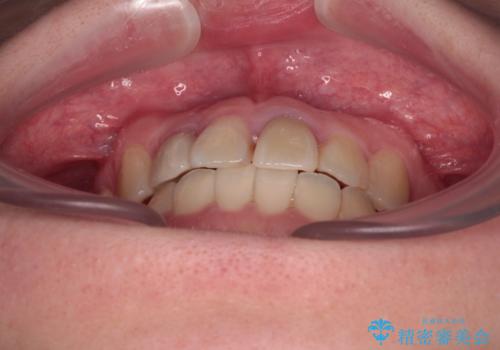

後戻りは軽度であり、インビザラインにて歯列を整え、その後にオールセラミッククラウンにて補綴治療を行うこととしました。

ご家庭やお仕事の都合で通院が途絶えた時期があり、治療は長期間となりましたが、無事に終えることができました。